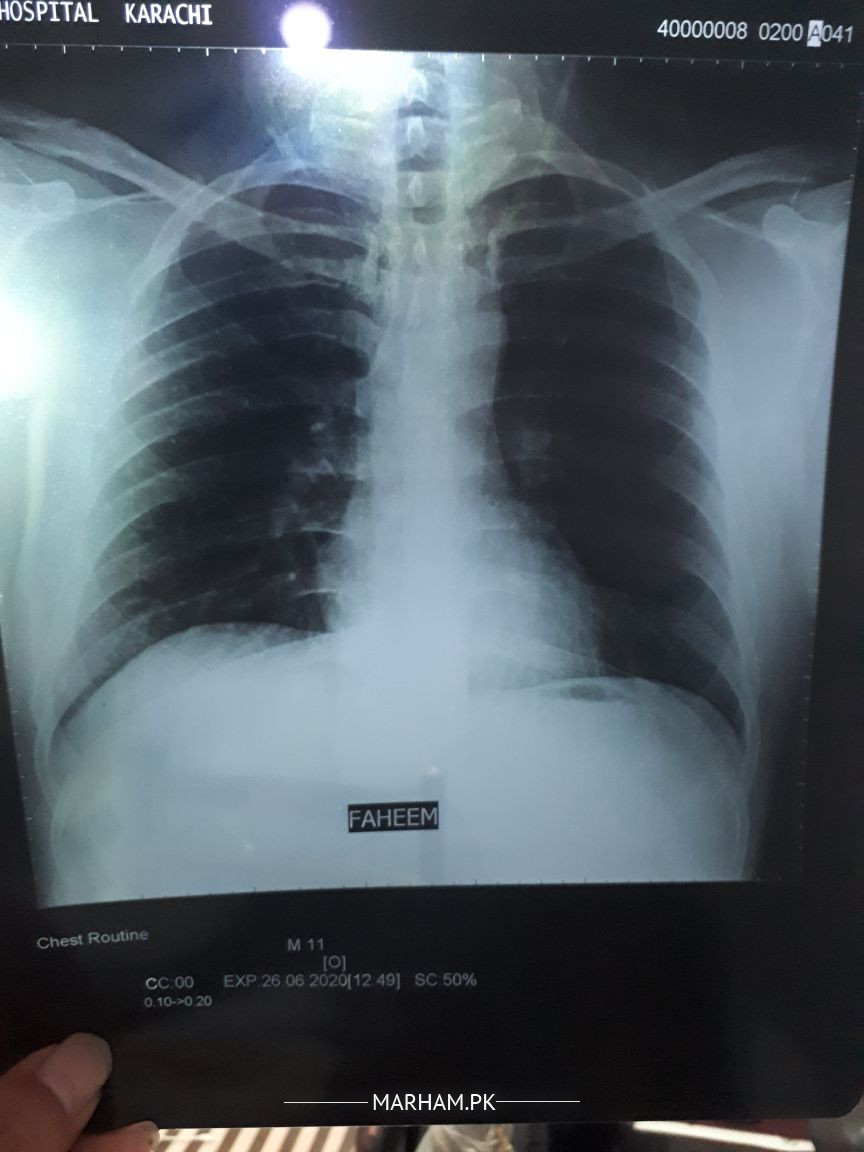

sir mera covid positive 11 june se mjhe sans ghut rha tha 11 june ko uske bad thek hugya tha or sore throat hueart beat inc chakr feal hurhe the smell or taste bhi khrab tha body aches

wo sab thek hugya pr 25 june se sans lene mai mushkil huri deep breath leta hu aesa lagta ghutan hai meri saturation 97 96 arahi oximeter pe xray attached kia hai

plz guide

medicie : calc1000 surbex z and 5 days se myteka 10mg lerha

Attach Photo here: